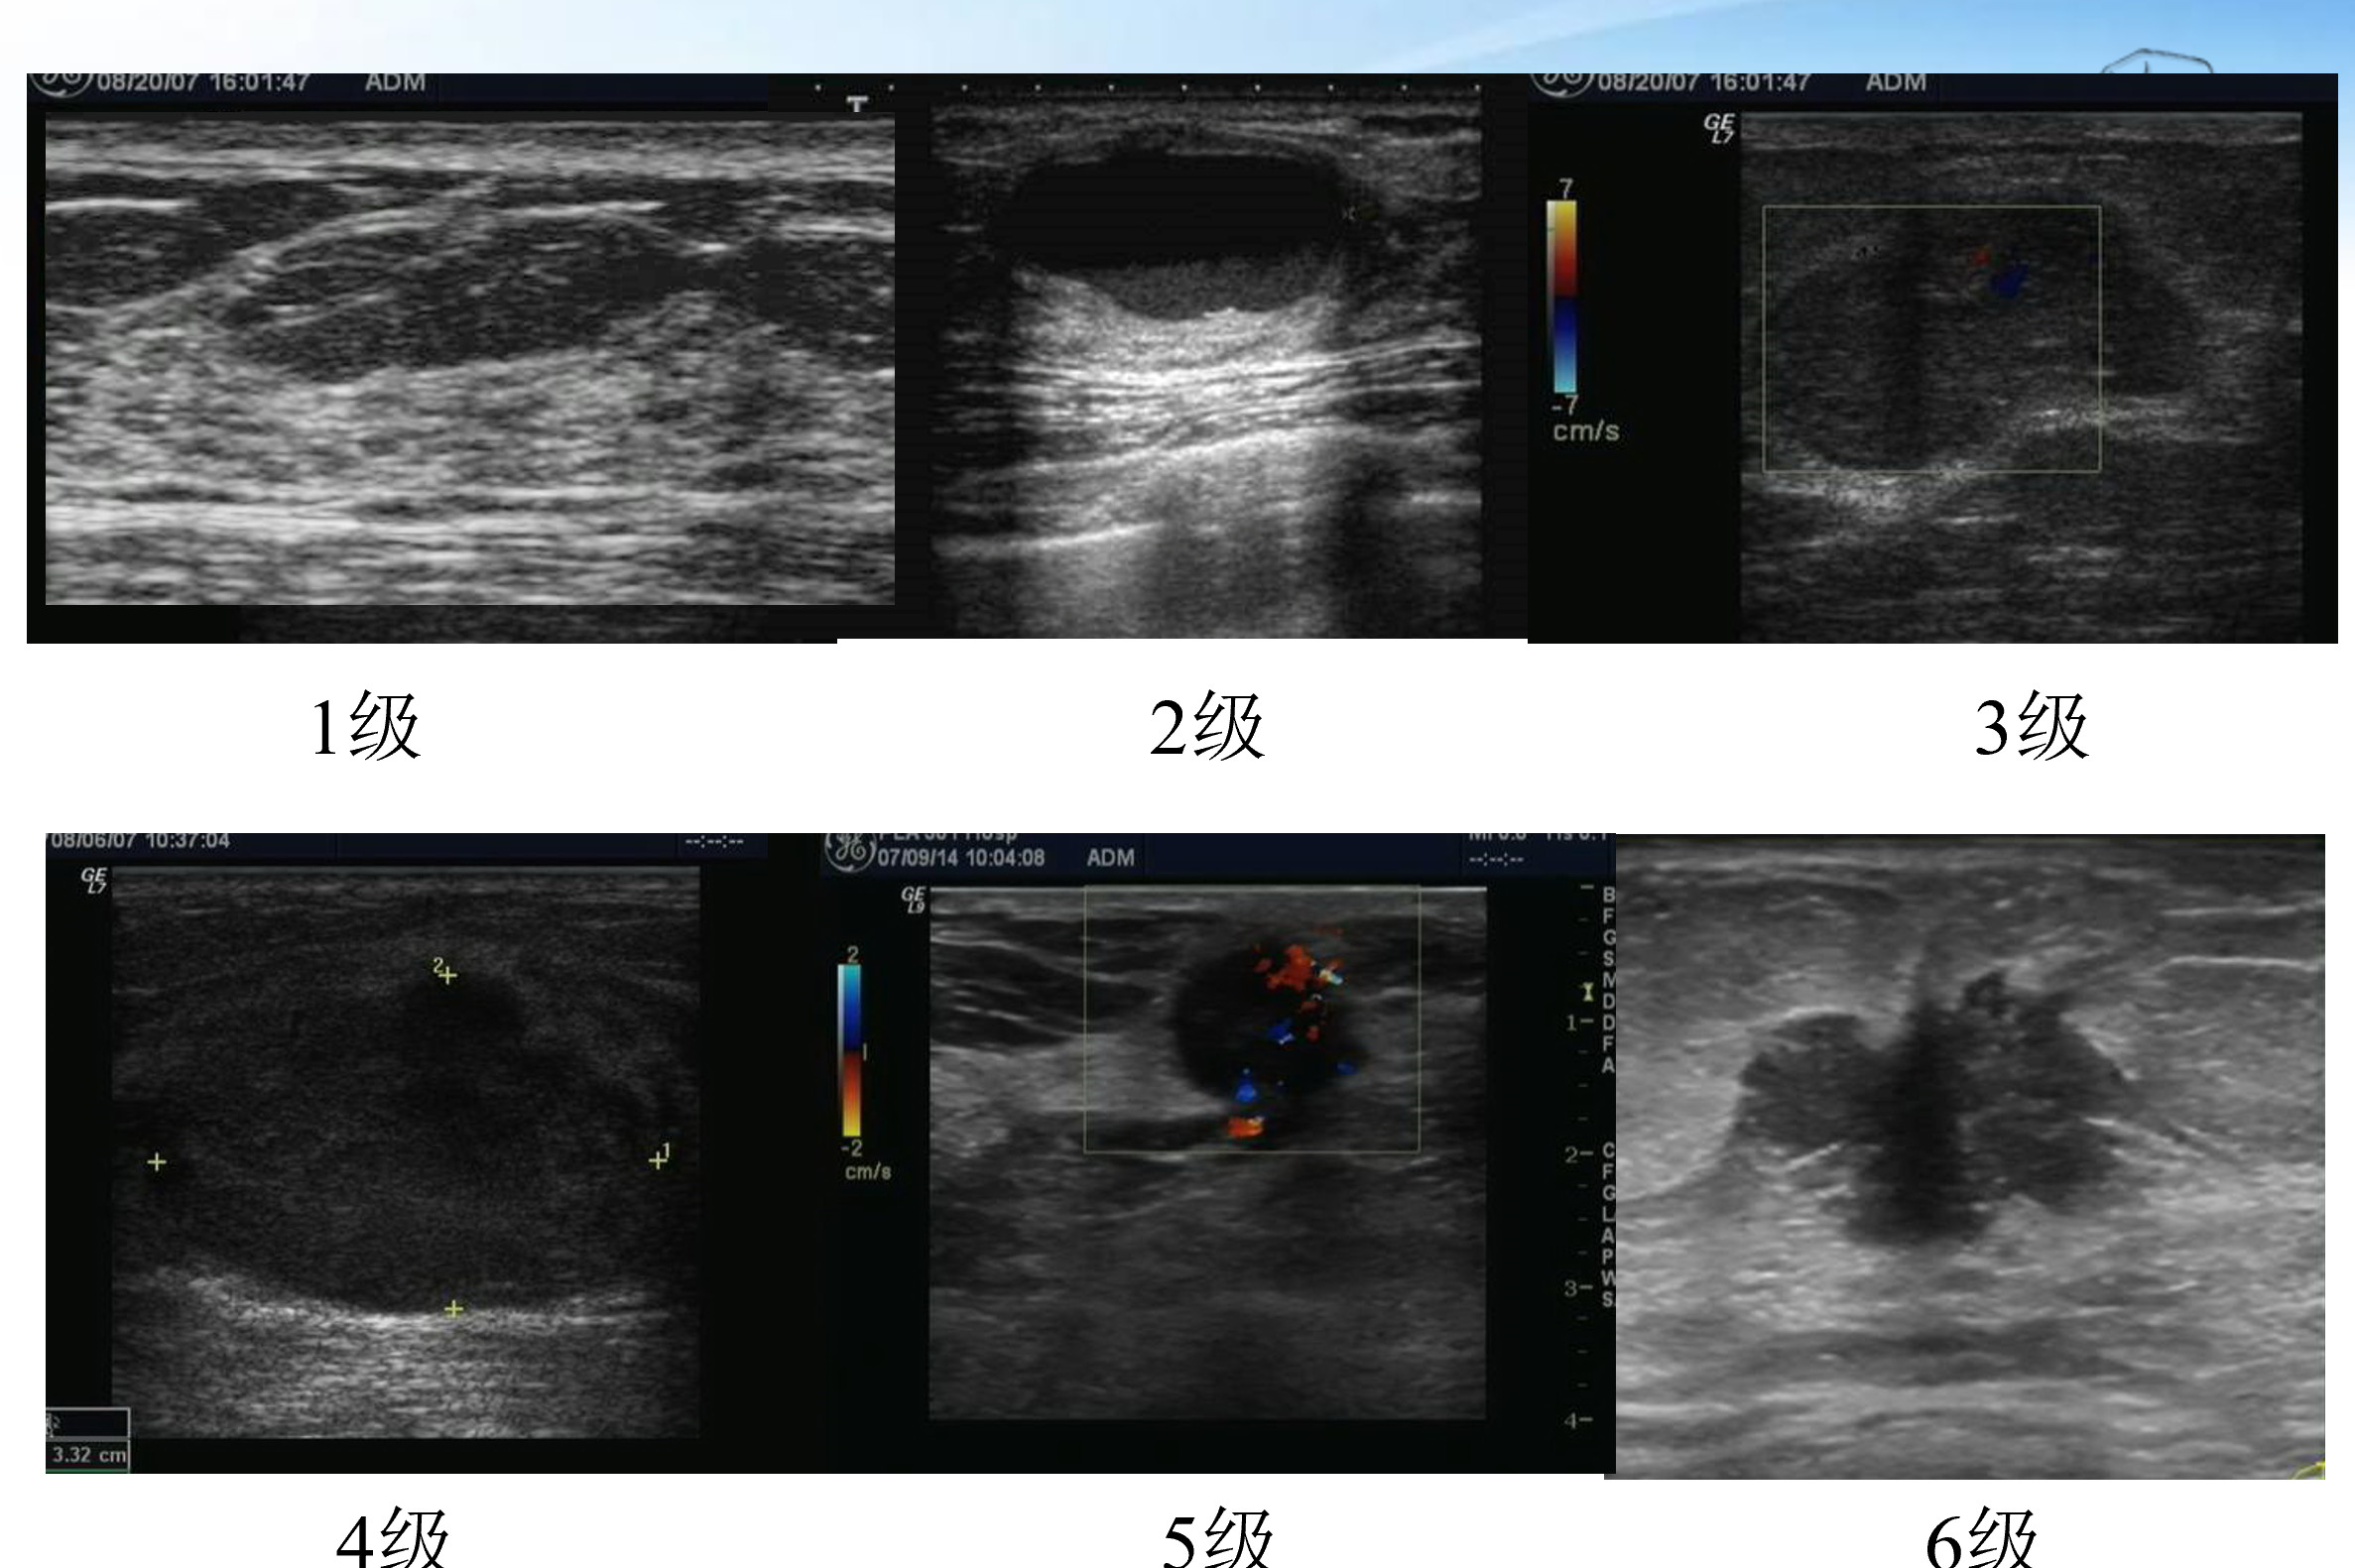

不同BI-RADS 分类的彩超征象

(1).比如:超声显示乳腺结构清晰,无肿块、无皮肤增厚、无微钙化等,腋窝有皮髓质分界清晰的淋巴结。结论:乳腺超声检查无异常,BI-RADS I类。

(2).比如:超声显示:肿块形态呈圆形或椭圆形;与皮肤平行或纵横比<1(即宽>高);边界清楚 ;周边缘(与周围组织之移行带或区域)窄而锐利;后方回声增强或无变化;无周围组织改变;较大的(≥0.5mm)钙化;内部无或者点状、少量、I级血流信号。凡符合前两条超声表现的基础后,有另外3条或3条以上者,评定为3类。报告结论为:BI-RADS 3类。

3类结节的彩超征象

乳腺彩超报告4类以上结节不建议保守治疗,最佳治疗措施是:穿刺活检或者手术切除。彩超医师发现结节至少具有有以下恶性征象的一项,才会做出BI-RADS分类4类及以上的诊断,即:病灶形状不规则、边界不清楚、毛刺状、成角、微小分叶、高回声晕、不平行的生长、内部微钙化、后方回声衰减、周围组织扭曲。

BI-RADS 4类及以上级别结节的彩超征象